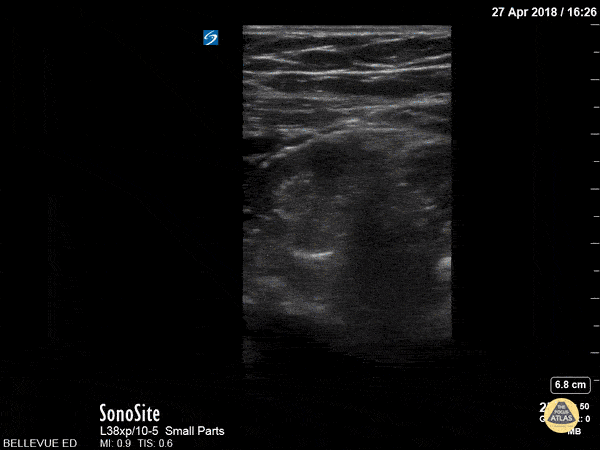

This clip shows a segment of the colon in long axis beneath layers of connective tissue and muscle. The peristalsis of the bowel is clearly visible as demonstrated by the motion of its inner contents. Hannah Kopinksi and Dr. Lindsay Davis - NYU Emergency Medicine